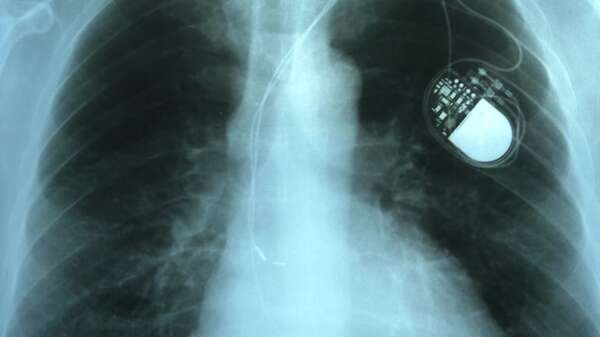

Marcapasos: cómo funciona, cuándo se indica y qué cambia en la vida diaria - Ciencia - ABC Color

Cómo funciona un marcapasos, en qué diagnósticos se indica —y en cuáles no—, qué riesgos reales tiene y qué cambia (y qué no) en la vida cotidiana. ...[Leer más]